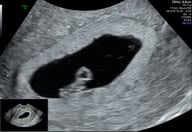

En esta sección celebramos la vida de nuestros pacientitos, esos pequeños grandes milagros que han pasado por RomoFetal. Aquí encontrarás recuerdos, testimonios y momentos especiales que compartimos con las familias que confiaron en nosotros para acompañarlos en su camino.

Más que pacientes, son parte de nuestra historia. Esta es nuestra forma de honrar cada comienzo y agradecer la confianza que nos brindan.

Nuestros Pacientitos